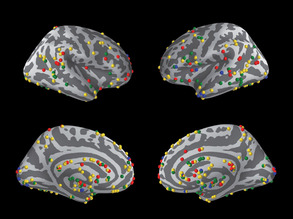

Joined-up Thinking